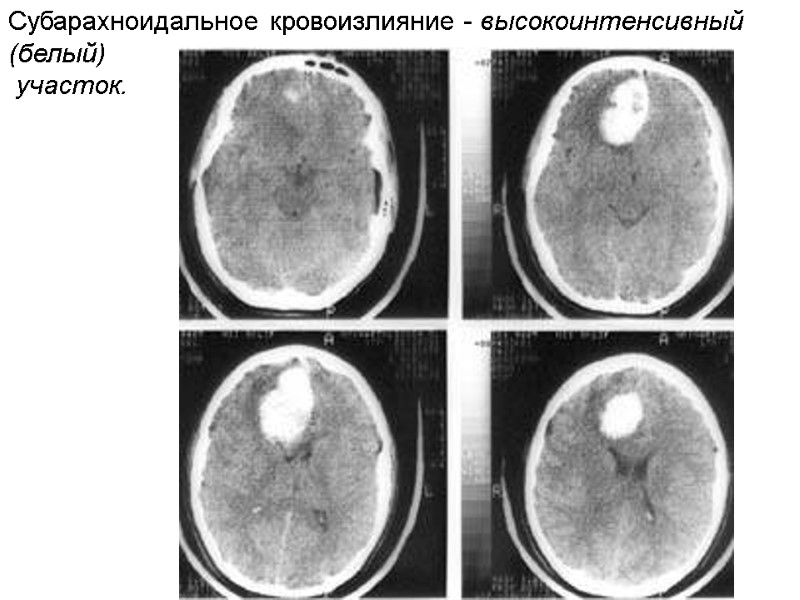

Вторая фаза проявляется при действии легкового автомобиля, когда центр тяжести тела пострадавшего находится выше места соударения. При фронтальном столкновении тело забрасывается на капот автомобиля. При этом повреждения образуются на той же поверхности тела, что и в 1 фазе. Отмечаются ссадины, кровоподтеки, реже – ушибленные раны мягких тканей головы, спины, груди и живота. Оскольчатые переломы костей свода и основания черепа, ушибы головного мозга, которые возникают как в месте удара, так и в области противоудара. Отмечаются закрытые переломы ребер, как локальные, так и конструкционные (непрямые), возникающие от деформации изгиба. В 1 и 2 фазах часто возникают повреждения внутренних органов. Вследствие ударного воздействия – кровоизлияния под капсулу и паренхиму органов, надрывы и разрывы органов грудной клетки и живота (корни легких, разрыв интимы крупных сосудов сердца, брызжейки, ворота почки и селезенки, печени) – локализуются всегда вблизи места приложения силы. Повреждения, вследствие сотрясения тела, морфологически выражаются в надрывах и разрывах связочного аппарата и сосудов, проходящих в них, кровоизлияния под капсулы и паренхиму органов. При очень сильных ударах (скорость автомобиля более 100 км/ч) – отрывы и размозжение внутренних органов, в т.ч. легких. В 3 фазе (отбрасывание тела и падение на грунт) образуются ссадины, кровоподтеки, рвано-ушибленные раны мягких тканей, в т.ч. на другой стороне тела, нежели в 1 и 2 фазах; переломы, в т.ч. костей черепа. В 4 фазе (скольжение и трение тела по грунту) – обширные, полосчатые ссадины (вдоль движения) – по которым можно установить направление движения; стертость мягких тканей и костей, которые располагаются на выступающих частях тела; на одежде – истончения, разрывы - поперечные, по отношению к направлению движения.

Переезд тела колесом автомобиля. Для переезда радиус колеса должен быть больше высоты тела лежащего человека. Если радиус равен высоте его – переезд практически невозможен. 1 фаза – удар и трение колесом. Повреждения неспецифичны – ссадины и кровоподтеки. В момент въезда колесом – возникает т.н. «первичный щипок» - широкая ссадина с отслойкой кожи от подлежащих тканей. При протаскивании тела колесом – полосовидные ссадины с отслойкой кожи от подлежащих тканей. Наиболее тяжелые повреждения образуются во 2 фазе – перекатывании через тело и сдавления его. Специфические повреждения – отпечатки протектора шины на коже: позитивные (т.е. следы выпуклых частей протектора) – это следы – наложения (грязи, пыли) (на одежде или коже); и негативные (т.е. отображающие форму и размеры углубленных участков протектора) – кровоподтеки. При переезде через голову («сокрушительный перелом черепа») обнаруживаются множественные оскольчатые переломы костей мозгового (свода и основания) и лицевого черепа. Череп деформируется (уплощается), острые края отломков изнутри прорывают кожу, через образовавшиеся отверстия выдавливается вещество мозга. Могут наблюдаться надрывы и отрывы ушных раковин.